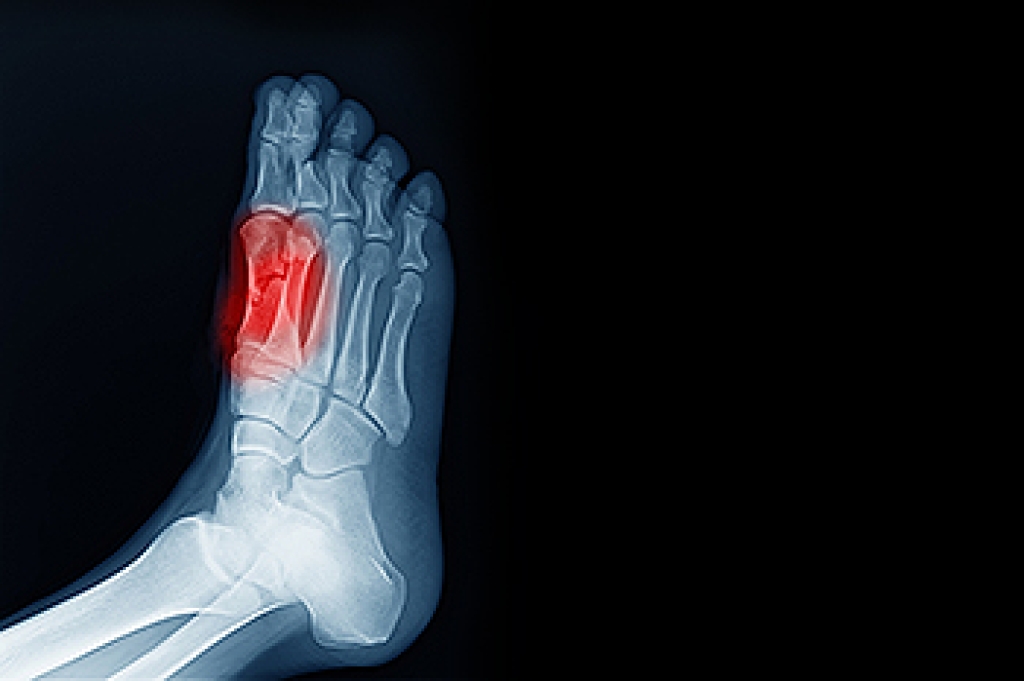

Poor dorsiflexion, or limited upward movement of the foot toward the shin, can interfere with walking and increase strain on other joints. Poor dorsiflexion is often the result of tight calf muscles, especially the gastrocnemius and soleus, which can restrict ankle movement. Previous ankle injuries, such as sprains that did not heal fully, may also lead to scar tissue or stiffness, further limiting motion. In some cases, compression or injury of the deep peroneal nerve, which controls the muscles responsible for dorsiflexion, may prevent the foot from lifting properly. Ankle joint restrictions or structural limitations related to genetics may also play a role. When dorsiflexion is impaired, the body may adapt by altering gait, which can place excessive stress on the knees, hips, and lower back. A podiatrist can evaluate the ankle’s range of motion, identify the underlying cause of the restriction, and recommend medical treatment or surgery, if necessary. If you have problems flexing your foot, it is suggested that you schedule an appointment with a podiatrist for a diagnosis and appropriate treatment.